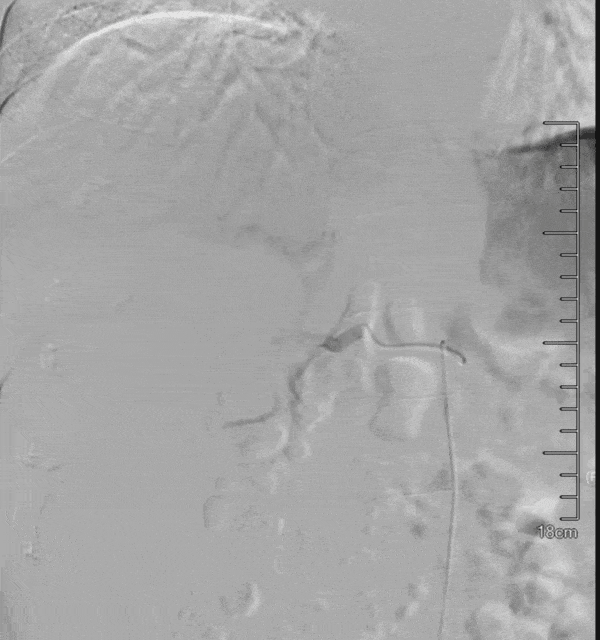

第二次D-TACE手术过程

于2020-9-24行D-TACE,术中造影发现肿瘤染色明显,较前缩小,再分别超选至肿瘤供血动脉,予表柔比星80mg+聚乙烯醇栓塞微球(蓝色型,100-300um)、2支无色型(300-500um),1支无色型(500-700um)栓塞肿瘤供血动脉,直到栓塞至肿瘤血管血流停滞。